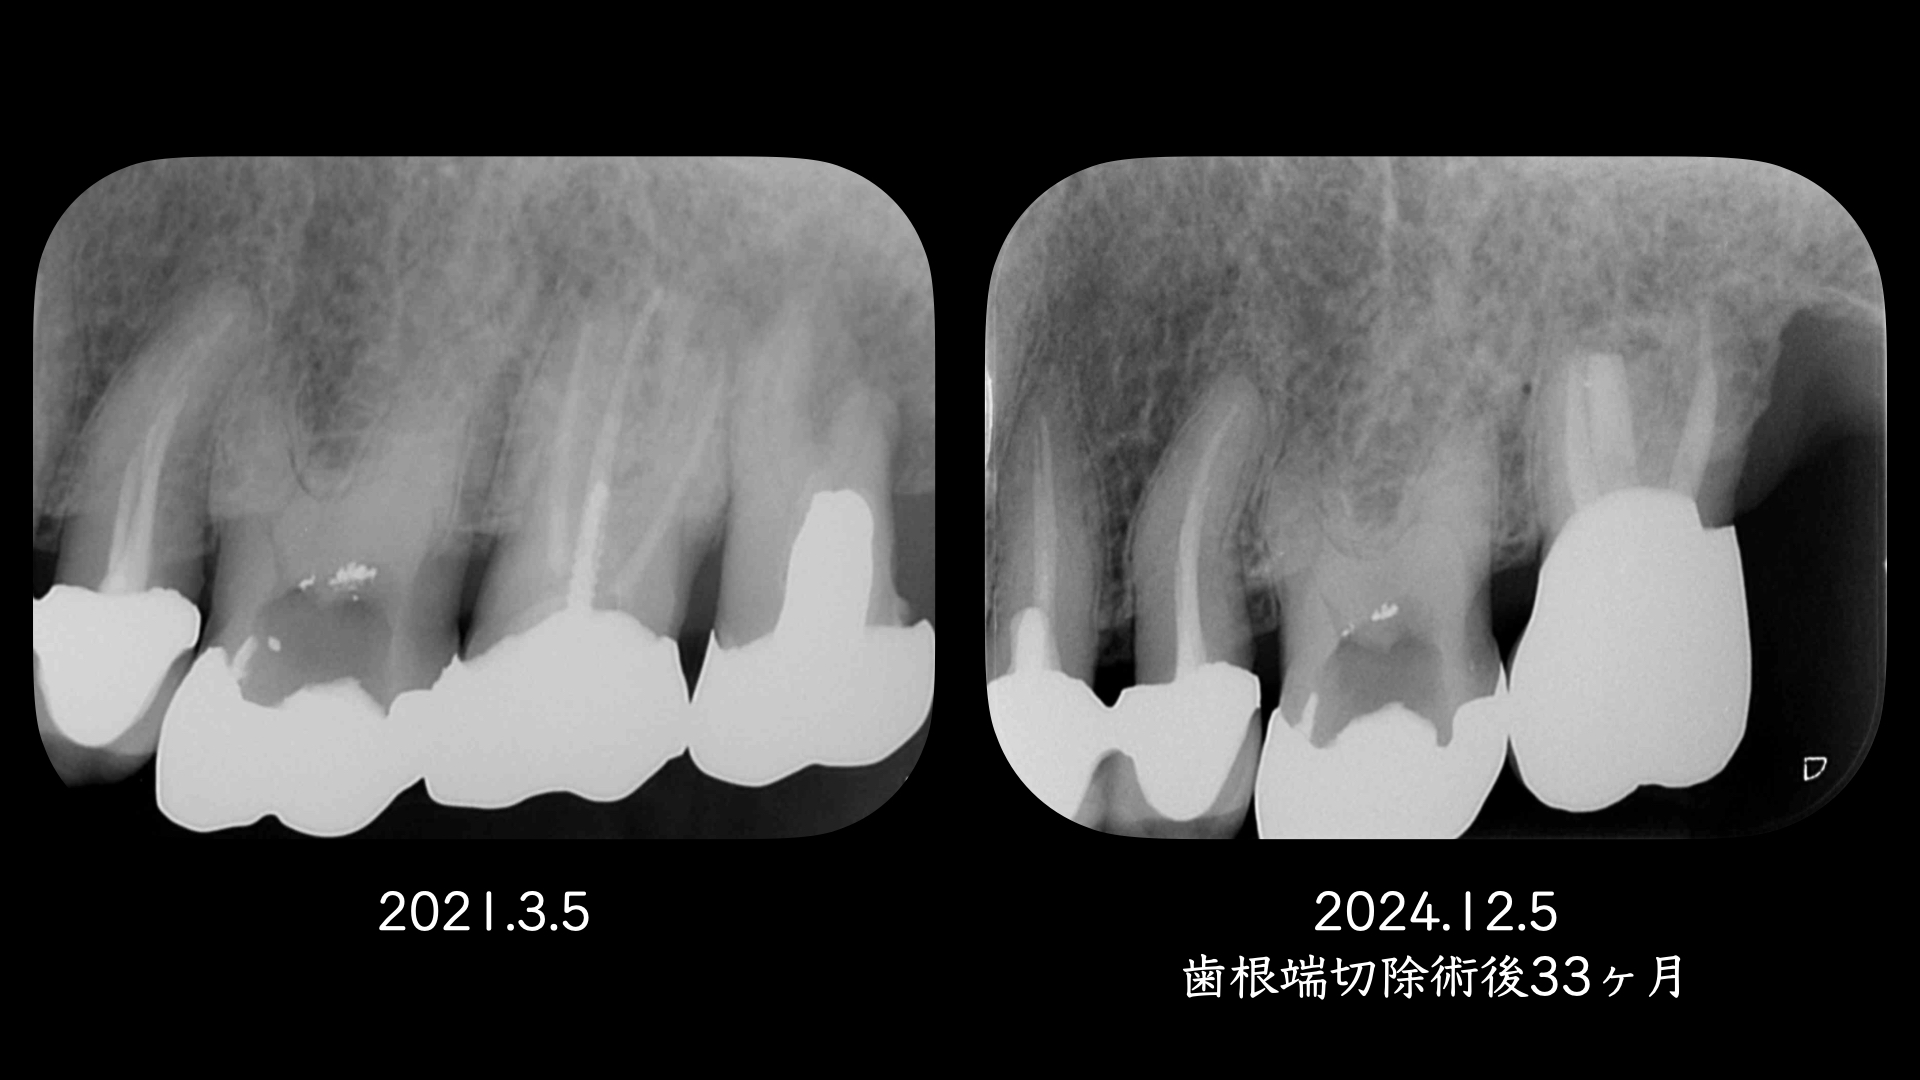

上顎口蓋根を歯根端切除(外科的歯内療法)した症例

右の画像のCT上で根尖部にかなり大きな透過像があります。

術後、歯根は骨に囲まれるように治癒にしました。

このように非外科的な治療のみでは治癒に導けない場合は、外科的歯内療法で保存できる可能性があります。